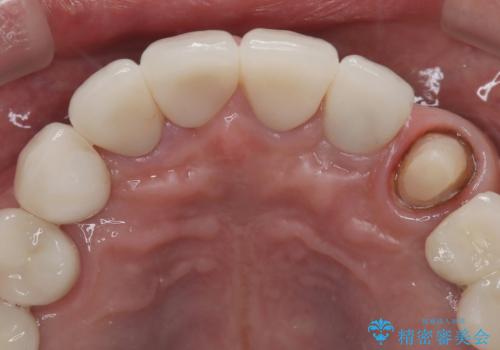

- 「被せ物が揺れている」を主訴に来院された患者様です。診査診断を行い被せ物が外れているのではなく、コアという土台ごと外れていたので、土台ごとやり変えた後オールセラミッククラウンで治療を行いました。

ファイバーコアという土台を建てるときに唾液が入ると接着に良くないのでラバーダムシートを使用しています。加えてマイクロスコープを使用しながら行う事で外れにくい土台を作ることが出来ます。その後、形成を行いシリコンで型取りしたのち、オールセラミッククラウンで修復しました。